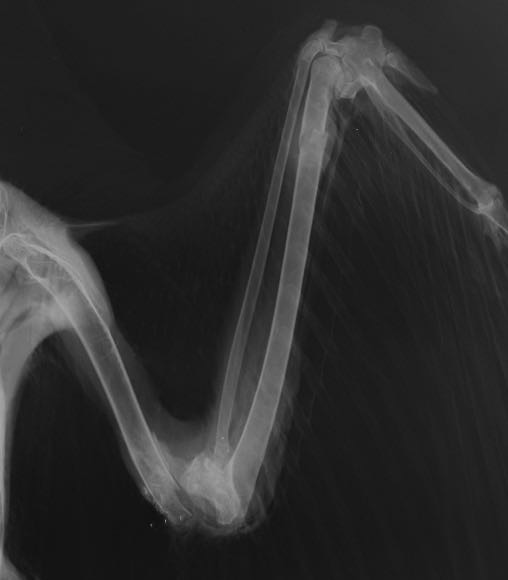

Red-tailed Hawk 18-569

18-569 was found in a field south of Pilot Rock with a suspicious wound on the left elbow. A radiograph showed a badly damaged elbow, small metal fragments, a fractured ulna and damage in the left wrist.

Further examination of the wing found both the entrance and exit wounds.